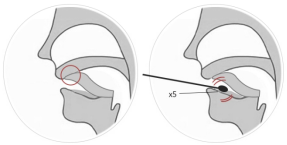

(1) Saliva sample collection: Do not eat or drink, including chewing gum or use tobacco products, 30 minutes before saliva sample collection. The tip of the tongue is pressed against the roof of the tongue to collect saliva from the base of the tongue. Place a sterile disposable cotton swab under the base of the tongue for at least 10 seconds, soak it completely in the saliva, and rotate it more than 5 times. (see picture 1)

Figure 1 Methodsfor saliva sample collection